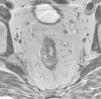

El cáncer de recto es una neoplasia con elevada incidencia en nuestro medio. Las distintas opciones terapéuticas que podrán aplicarse en cada caso van a depender fundamentalmente de la extensión que presente el tumor en el momento del diagnóstico. Por esto, los radiólogos tenemos un papel central en su tratamiento. En el presente texto se discuten la técnica radiológica óptima, algunos aspectos anatómicos fundamentales y la semiología aceptada en la interpretación de los distintos estudios de imagen que se realizan a estos pacientes, además de su rendimiento, y una visión general del pronóstico y de las distintas opciones terapéuticas. Su conocimiento es muy útil para participar en equipos formados por diferentes especialistas y comprender la trascendencia de la información aportada por la interpretación de los estudios que realizamos a estos pacientes.

Rectal cancer has a high incidence in our area. The different treatment options that can be used in each case depend fundamentally on the extension of the tumor at the time of diagnosis. Thus, radiologists have a central role in the management of this disease. We discuss the optimum imaging technique for staging rectal cancer, some fundamental histological aspects, and the accepted semiology in the interpretation of different imaging studies carried out in these patients, as well as the diagnostic performance of each technique. We provide a general overview of the prognosis and different treatment options. This knowledge is very useful for radiologists participating in multidisciplinary teams and for understanding the transcendence of the information provided by image interpretation in these patients.